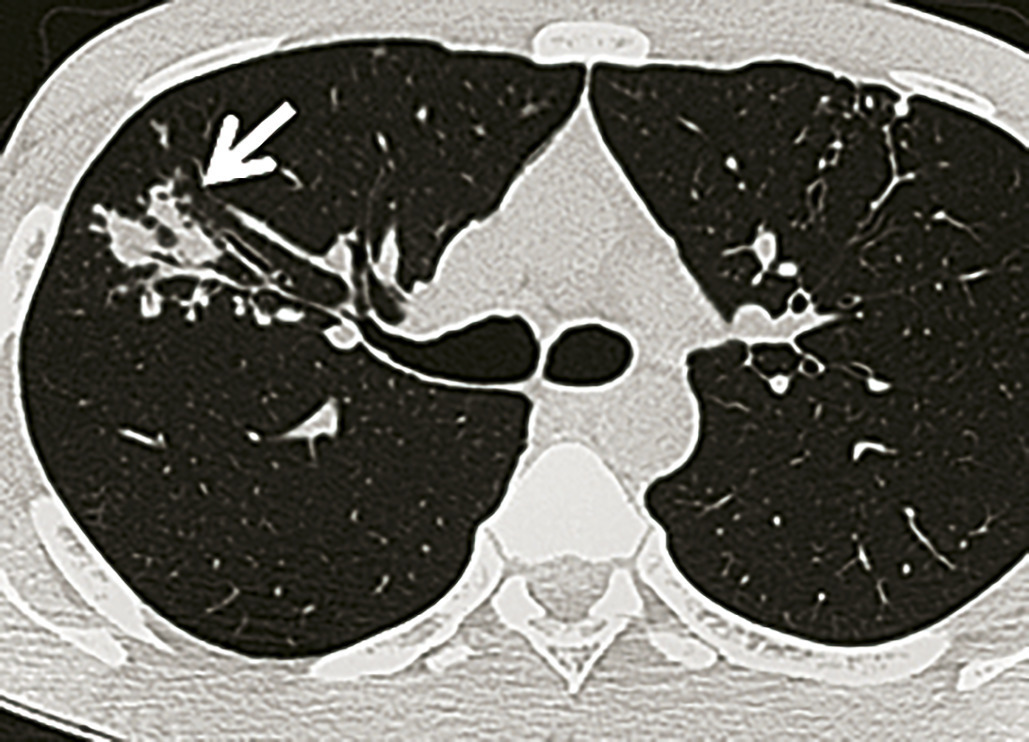

Imagerie (fig.1-4)

L’imagerie thoracique (radiographie, tomodensitométrie plus précise) révèle des opacités et modifications morphologiques de plusieurs types ± associées : atteintes bronchiolaires, bronchocèles, nodules acinaires, masses ± excavées, formes pneumoniques, rétractions lobaires, adénopathies médiastinales, pleurésies, miliaires.